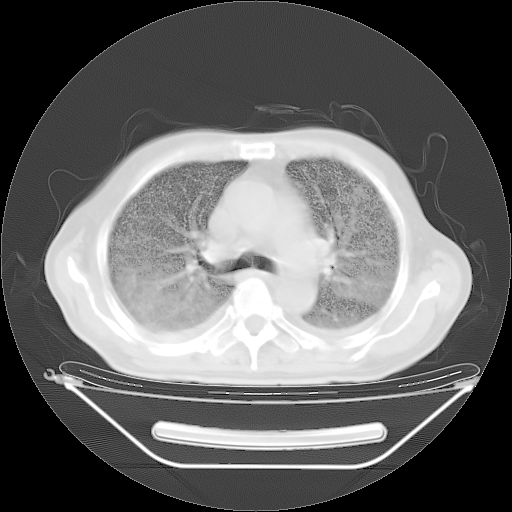

今天复查肺部CT,发现双肺广泛磨玻璃样改变。所以我把3月19日和5月9日相隔50天的肺部CT上传。请大家会诊。

2009年3月19日肺部CT片。

2009年3月19日肺部CT